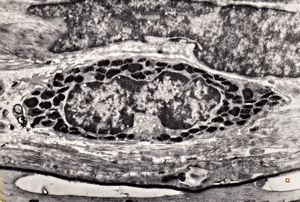

M,41y. | ribosome-lamella complex in tricholeukocyte -hairy cell leukemia, spleen